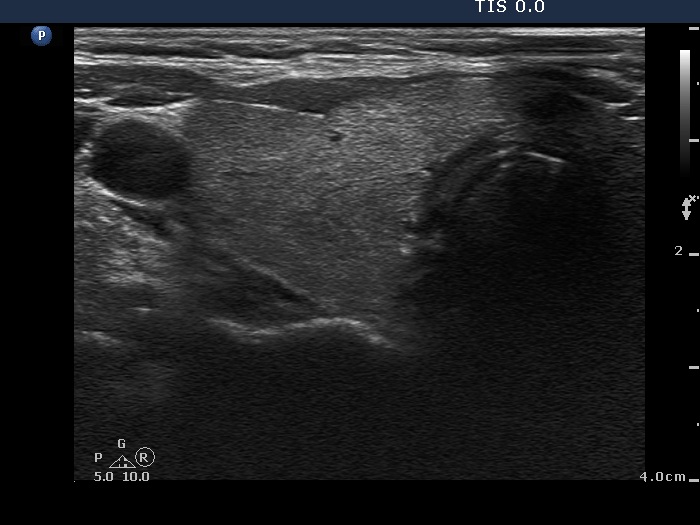

Intranodular hyperechogenic figures - case 1789 (ultrasonographic picture 1)

Right lobe, horizontal view

Right lobe, transverse view. This is an intact lobe.